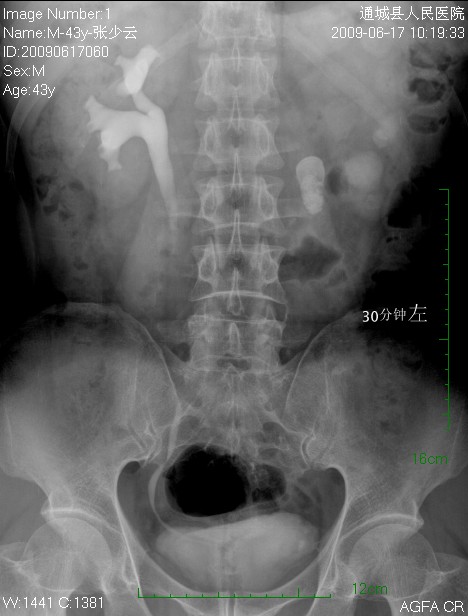

标题: CL1983:尿路结石

左侧输尿管结石并左肾积水